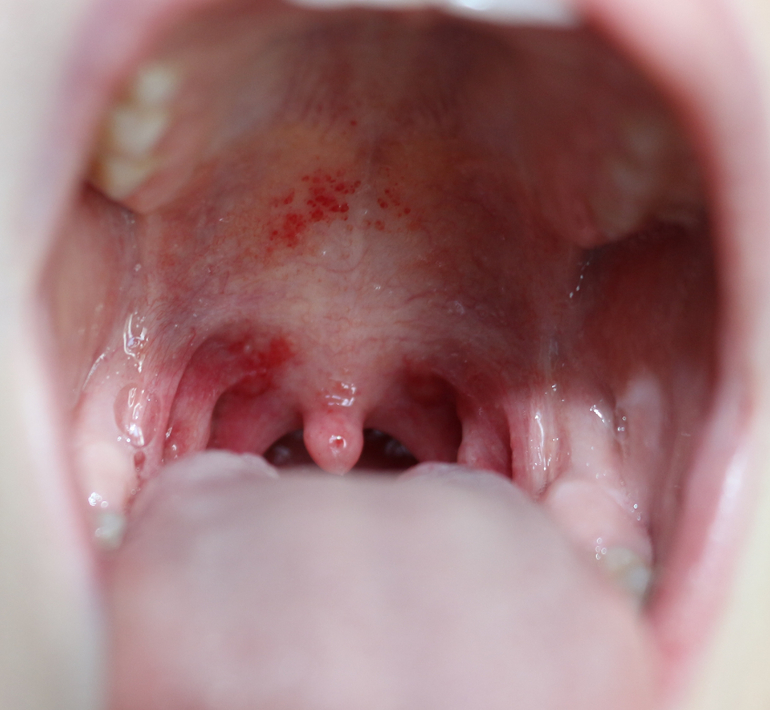

Горло

ЗдоровьеКак всегда некстати заболела дочка(( В 4-6 лет у нее часто случались ОРВИ с острым фарингитом, и горло я у нее видела всякое, но такого, как в этот раз, я не видела никогда.

Врача на дом вызывать смысла не имеет - придет наша участковая, а о ее компетентности, к сожалению, вопрос не стоит. Поэтому врача на дом не вызываем никогда, сами ходим к другому врачу. В поликлинику, соответственно. можем попасть только завтра. У меня вопрос к тем, кто с таким сталкивался - что это?